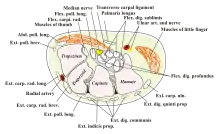

In the human body, the carpal tunnel or carpal canal is the passageway on the palmar side of the wrist that connects the forearm to the hand.[1]

The tunnel is bounded by the bones of the wrist and flexor retinaculum from connective tissue. Normally several tendons from the flexor group of forearm muscles and the median nerve pass through it. There are described cases of variable median artery occurrence.

Structure

The carpal bones that make up the wrist form an arch which is convex on the dorsal side of the hand and concave on the palmar side. The groove on the palmar side, the sulcus carpi, is covered by the flexor retinaculum, a sheath of tough connective tissue, thus forming the carpal tunnel. On the side of the radius, the flexor retinaculum is attached to the scaphoid bone, more precisely its tubercle, as well as the ridge of trapezium. On the ulnar side, it is attached to the pisiform and hook of hamate.[4]

The tendons of the flexor digitorum superficialis and profundus pass through a common ulnar sheath, while the tendon of the flexor pollicis longus passes through a separate radial sheath. The mesotendon shared by these tendons is attached to the radial and palmar walls of the carpal tunnel.[4]

Superficial to the carpal tunnel and the flexor retinaculum, the ulnar artery and ulnar nerve pass through the ulnar tunnel/Guyon's canal.[4]

Ten structures pass through the carpal tunnel, most of them flexor tendons[2] (not the muscles themselves):

- flexor digitorum profundus (four tendons)

- flexor digitorum superficialis (four tendons)

- flexor pollicis longus (one tendon)

- Median nerve between tendons of flexor digitorum profundus and flexor digitorum superficialis

The flexor carpi radialis (one tendon) is often incorrectly stated to travel within the carpal tunnel. More precisely, it travels within the fibers of the flexor retinaculum which forms the roof of the carpal tunnel, rather than running inside the tunnel itself.